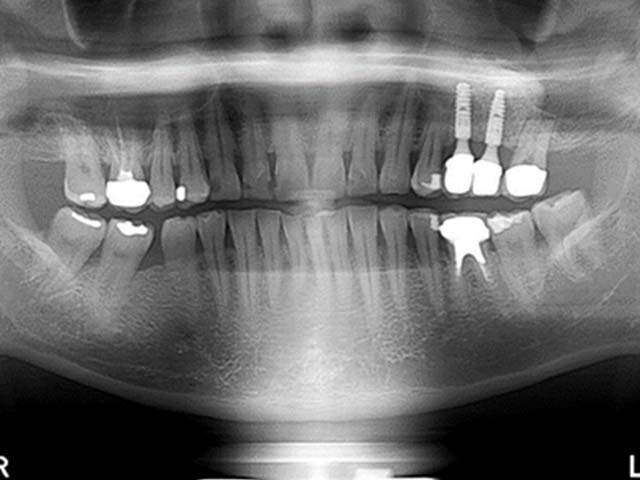

鼻竇增高術(側窗) 首頁 案例分享 人工植牙 鼻竇增高術(側窗) 鼻竇增高術(側窗) 製作多年的牙橋,牙根斷裂,發炎 鼻竇增高術 側面開窗 抬高鼻竇 鼻竇增高術 置入骨粉 覆蓋再生膜,保護骨粉 術後追蹤,傷口良好 裝戴正式假牙 完成 8年追蹤 左上牙根斷裂 植牙重建 九年追蹤